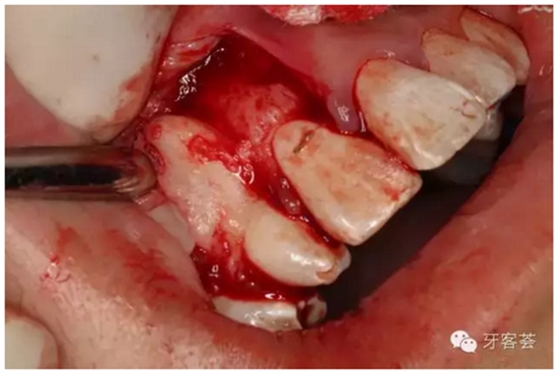

圖6:切開、翻瓣、暴露13牙冠。

圖7:12的牙根畸形肥大。正畸要求拔掉12.